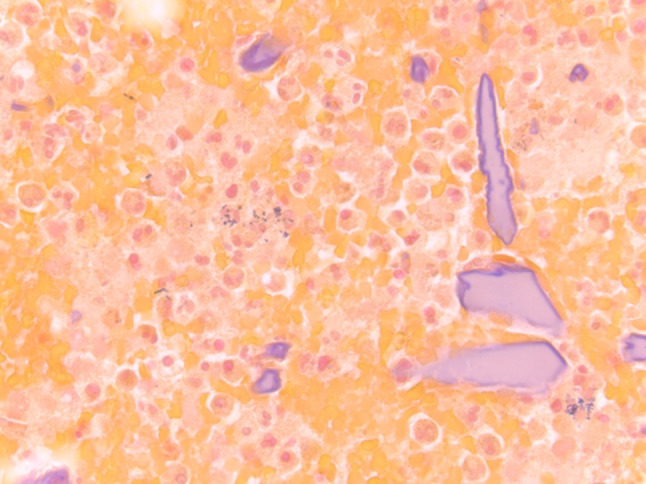

Fig. 11.

a Amylase crystalloids in a FNA smear (Diff Quick stain, magnification × 20). b Fragmented amylase crystalloids shown in a FNA cell block (H&E stain, magnification × 20)